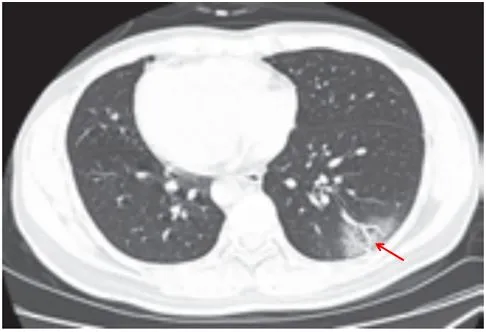

病灶以肺外围背侧为主,以两肺下叶为著,与胸膜常紧贴,提示新冠肺炎病变多首先侵犯皮层肺组织的细支气管及肺泡上皮,病灶分布逐步从外周向中央扩展(图 2-1)

图2-1 早期病灶多数分布贴近胸膜(共4张)